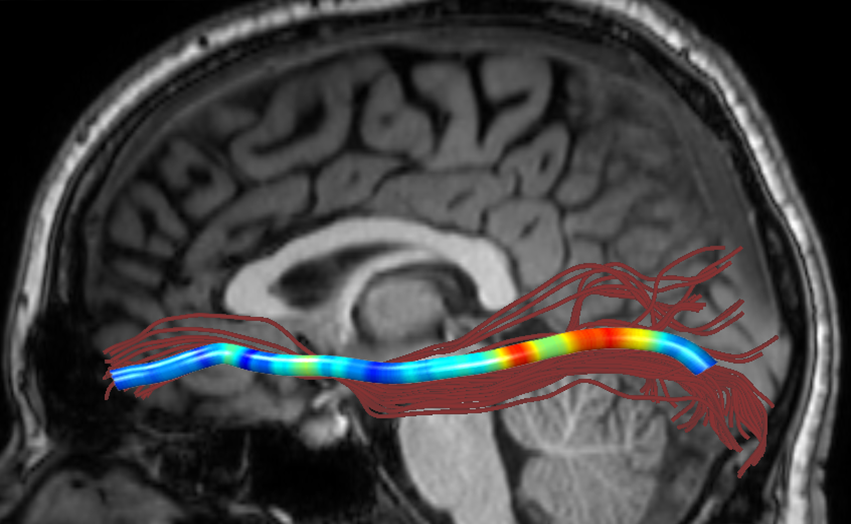

We performed pairwise comparison between two scans of a 32-year-old basketball player, diagnosed with mild occipital traumatic brain injury and frontal hemorrhage due to contrecoup impact, acquired one week and 6 months post-injury. The hemorrhagic lesion at the frontal right hemisphere of the player is no longer visible in the FLAIR image acquired 6 months after injury (Fig. 2a). Local differences between corresponding, longitudinal FA- and MD-FFDD profiles of the FMT (chosen due to its proximity to the lesion area) are shown in Fig. 2d. Figs. 2b-c present color-coded FMT to visually demonstrate these differences. Results show significant longitudinal variability at the right hemisphere part of the tract, corresponding to the lesion area, and relatively minor differences along the rest of the tract. These results should be considered as a proof of concept, validating the FFDD analysis results for the detection and localization of mTBI-related variabilities between fiber bundles.

| ONE WEEK | ![]() |

![]() |

FA-FFDD |

| 6 MONTHS | ![]() |

MD-FFDD |

| (a) FLAIR | (b) FA-FFDD | (c) MD-FFDD | (d) Local Differences |